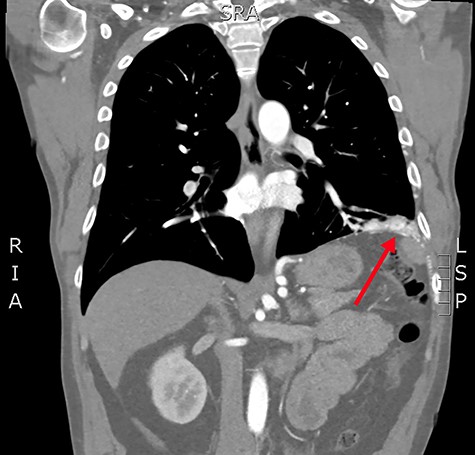

Coronal slice from the CTPA, demonstrating the large, complex PAVM in the left lung’s lower lobe, with some subdiaphragmatic extension (red arrow).

Concerned for pulmonary embolism (PE), a computed tomography pulmonary angiogram (CTPA) was arranged. PE was excluded; however, it did reveal a complex left-sided intra- and extrathoracic vascular malformation within the anteromedial segment of the left lung’s lower lobe, the lingula segment, the subdiaphragmatic space and the left chest-wall (Figs. 1 and 2). The arterial supply derived from large tortuous vessels arising from a combination of the coeliac trunk, six posterior intercostal arteries and the left inferior phrenic artery (Fig. 3). It then communicated with the left upper and lower lobe subsegmental pulmonary arteries, and the left lower lobe pulmonary vein. Subsequent echocardiography was normal, with no significant valvular pathology—evidencing that the pansystolic murmur was an arteriovenous bruit.